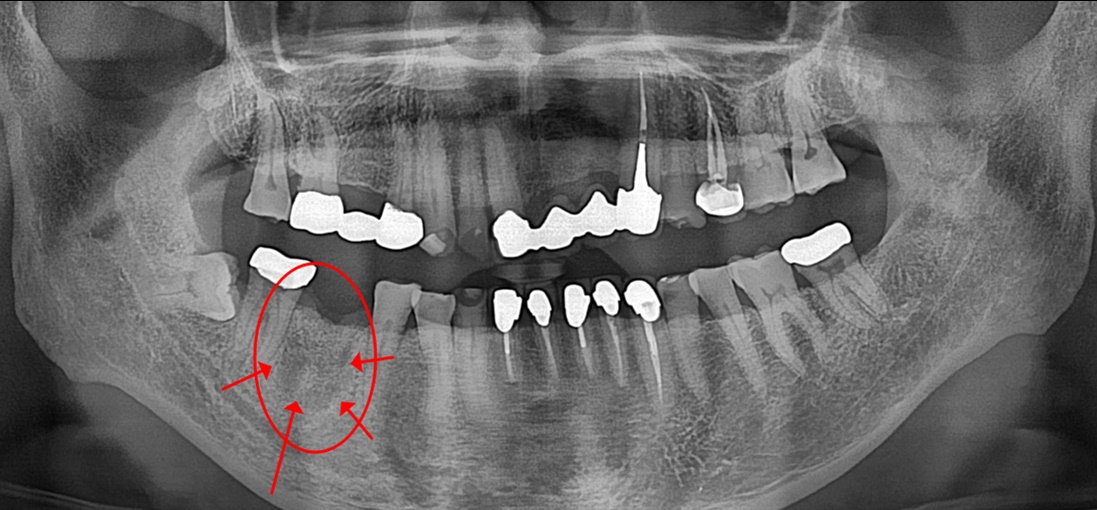

치료 전 파노라마

위의 사례분의 사진도 보시면 통증이 없었기 때문에 방치하고 계시다가 잇몸이 붓고 아파서 내원 하셨습니다.

엑스레이상 #46 치아 주위 치조골은 모두 소실되었고 즉시 임플란트 치료를 하기에도 곤란한 상태였습니다.